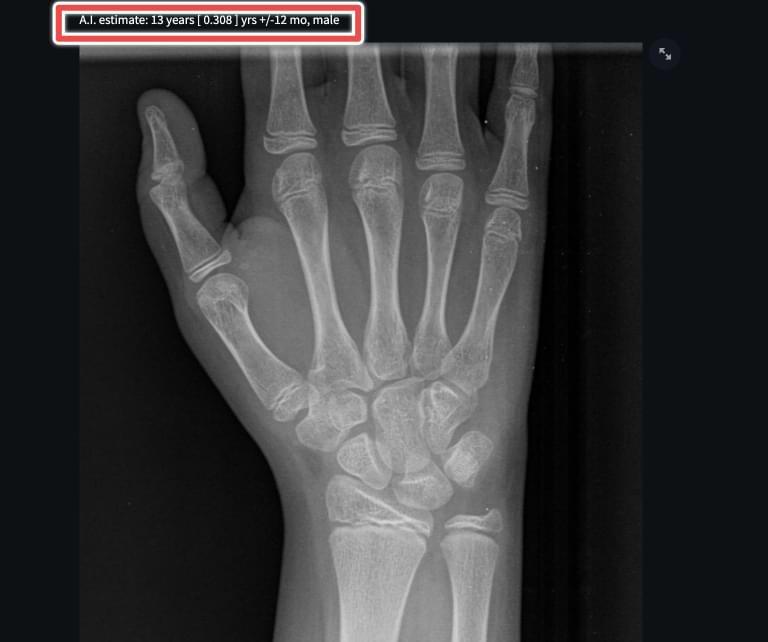

AI for accurate bone age diagnosis Radailogy How Accurate Is Bone Age In this review, we compare and present the spectrum of current. However, data obtained from the assessment of bone age can be widely used both in medical or nonmedical settings. In modern studies, researchers have explored the accuracy of bone age across. Identify the anatomical structures involved in assessing bone age. Review the clinical relevance of determining bone age. Current. How Accurate Is Bone Age.

IB Lab PANDA Pediatric Bone Age Ferrum Health How Accurate Is Bone Age Describe the indications for determining bone age. However, data obtained from the assessment of bone age can be widely used both in medical or nonmedical settings. The determination of bone age is important to properly assess and guide the evaluation of short or tall stature, impaired or accelerated growth, and delayed or early puberty (10). In recent years, new methods. How Accurate Is Bone Age.

Figure 1 from Pediatric Bone Age Assessment using Deep Learning Models How Accurate Is Bone Age However, data obtained from the assessment of bone age can be widely used both in medical or nonmedical settings. In this review, we compare and present the spectrum of current. Review the clinical relevance of determining bone age. Bone age is one of biological indicators of maturity used in clinical practice and it is a very important parameter of a. How Accurate Is Bone Age.